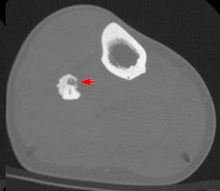

Radiographs in osteoid osteoma typically show a round lucency, containing a dense sclerotic central nidus (the characteristic lesion in this kind of tumor), surrounded by sclerotic bone. The nidus is seldom larger than 1.5 cm.

The lesion can in most cases be detected on CT scan, bone scans and angiograms. Plain radiographs are not always diagnostic. MRI adds little to the CT findings which are useful for localisation. Radionuclide scanning shows intense uptake which is useful for localisation at surgery using a hand held detector, and for confirmation that the entire lesion has been removed.[8][9]